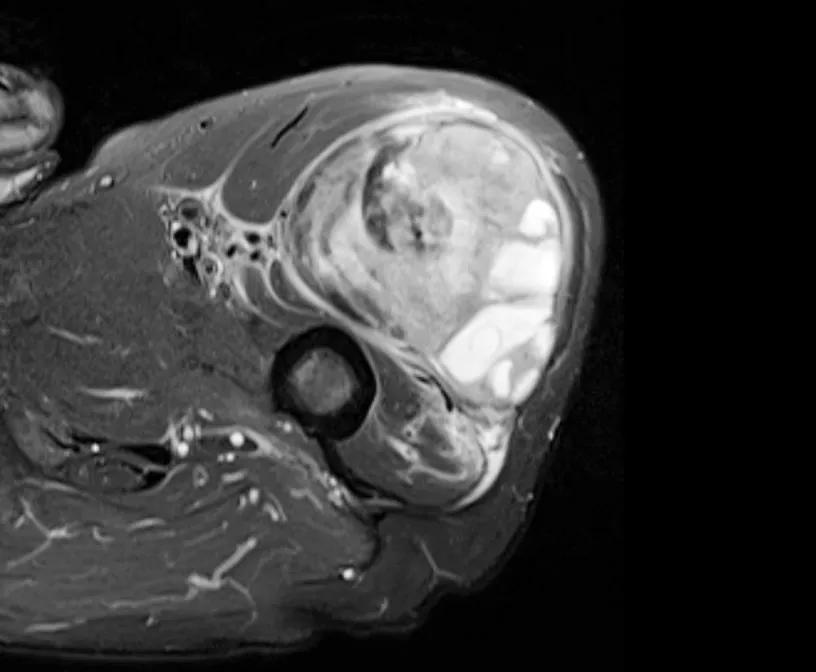

MRI of soft tissue sarcoma

Fifty years ago, soft tissue sarcoma was treated primarily with amputation. Since the development and refinement of MRI, it has become easier for surgeons to understand the extent of a tumor and, thus, more safely remove the tumor without amputation. Dr. Nystrom refers to an MRI scan as his “map” for a surgical resection.